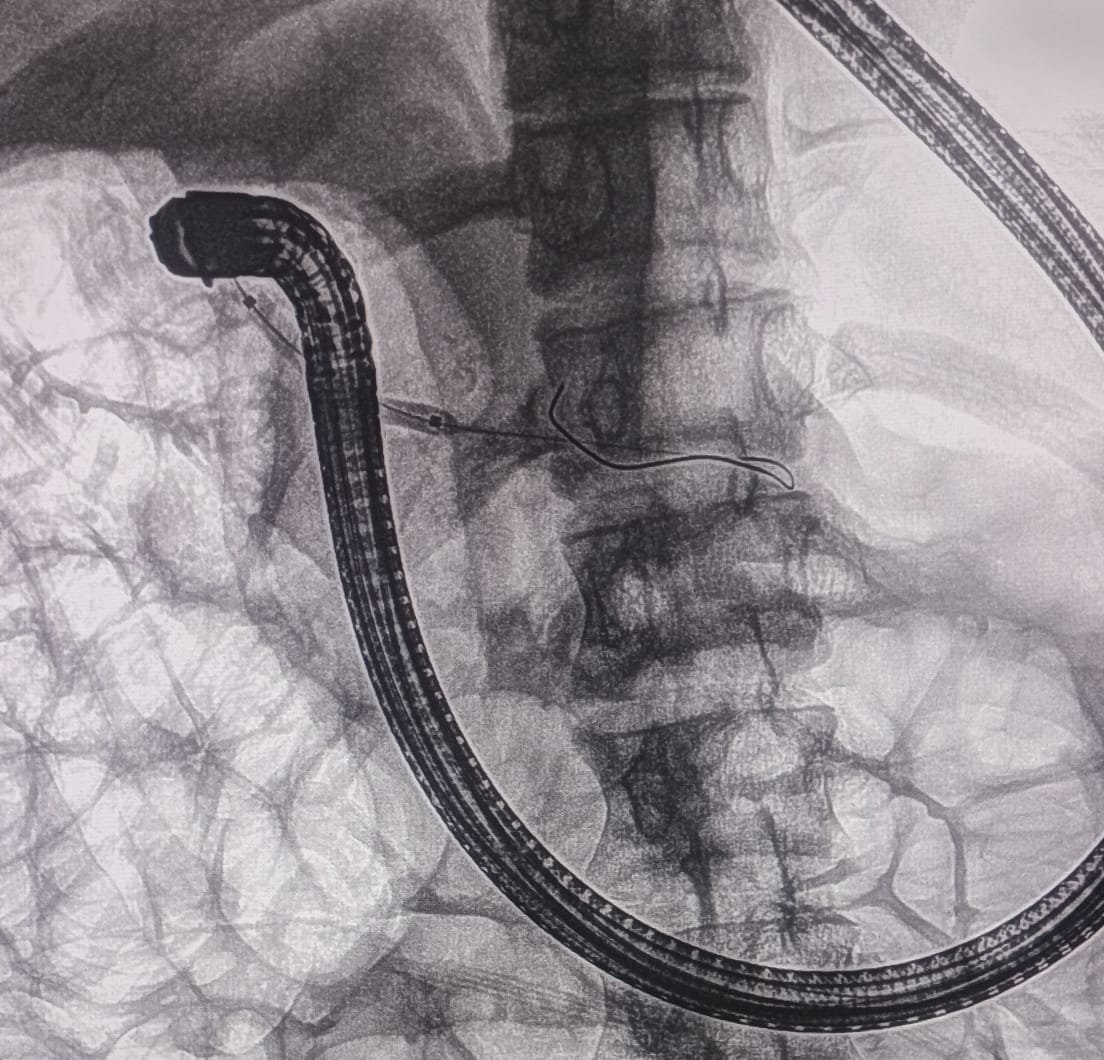

EUS Pancreatogastrostomy was successfully performed. The pancreatic duct was identified and punctured under EUS guidance. A wire was placed into the PD, and the tract was dilated with a 6Fr cystotome. A 10mm x 60mm fully covered metallic SEMS was placed.

A plastic stent was placed inside the metallic stent to stabilize and prevent migration of the metallic stent.

EUS Pancreatogastrostomy Procedure

EUS-guided Pancreatogastrostomy with Stent Placement